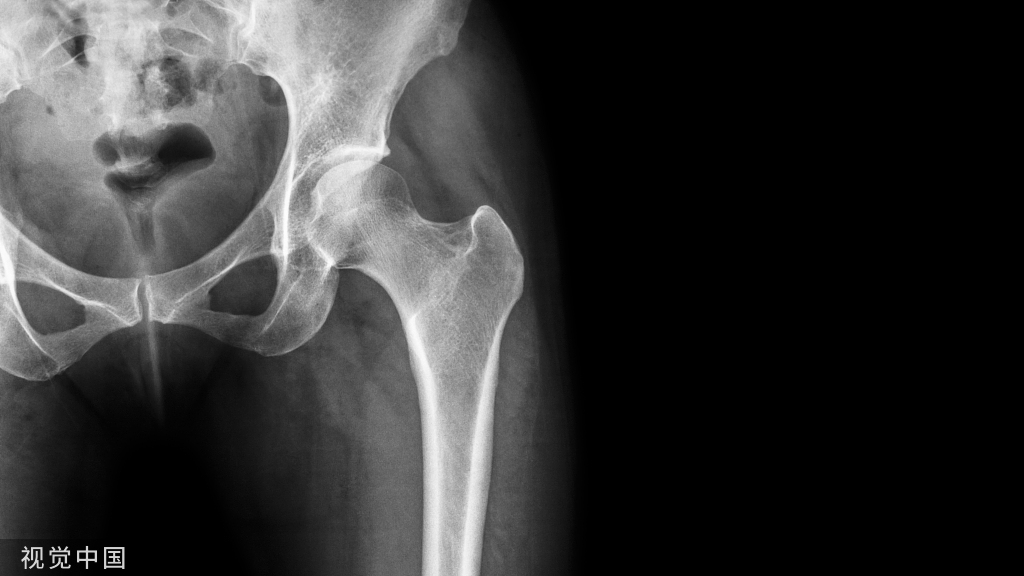

老年人股骨粗隆间骨折疾病治疗的时候,利用机器人导航髓内钉固定属于比较理想的方式,且手术时间比较短,创伤也明显更小,且存在着髋关节功能有效恢复的效果。

根据骨折的类型实施分类,明确得出在骨折部位的间隙使结构更能够承受更高的种植体应力和更大的碎片间运动,优化股骨内固定术。